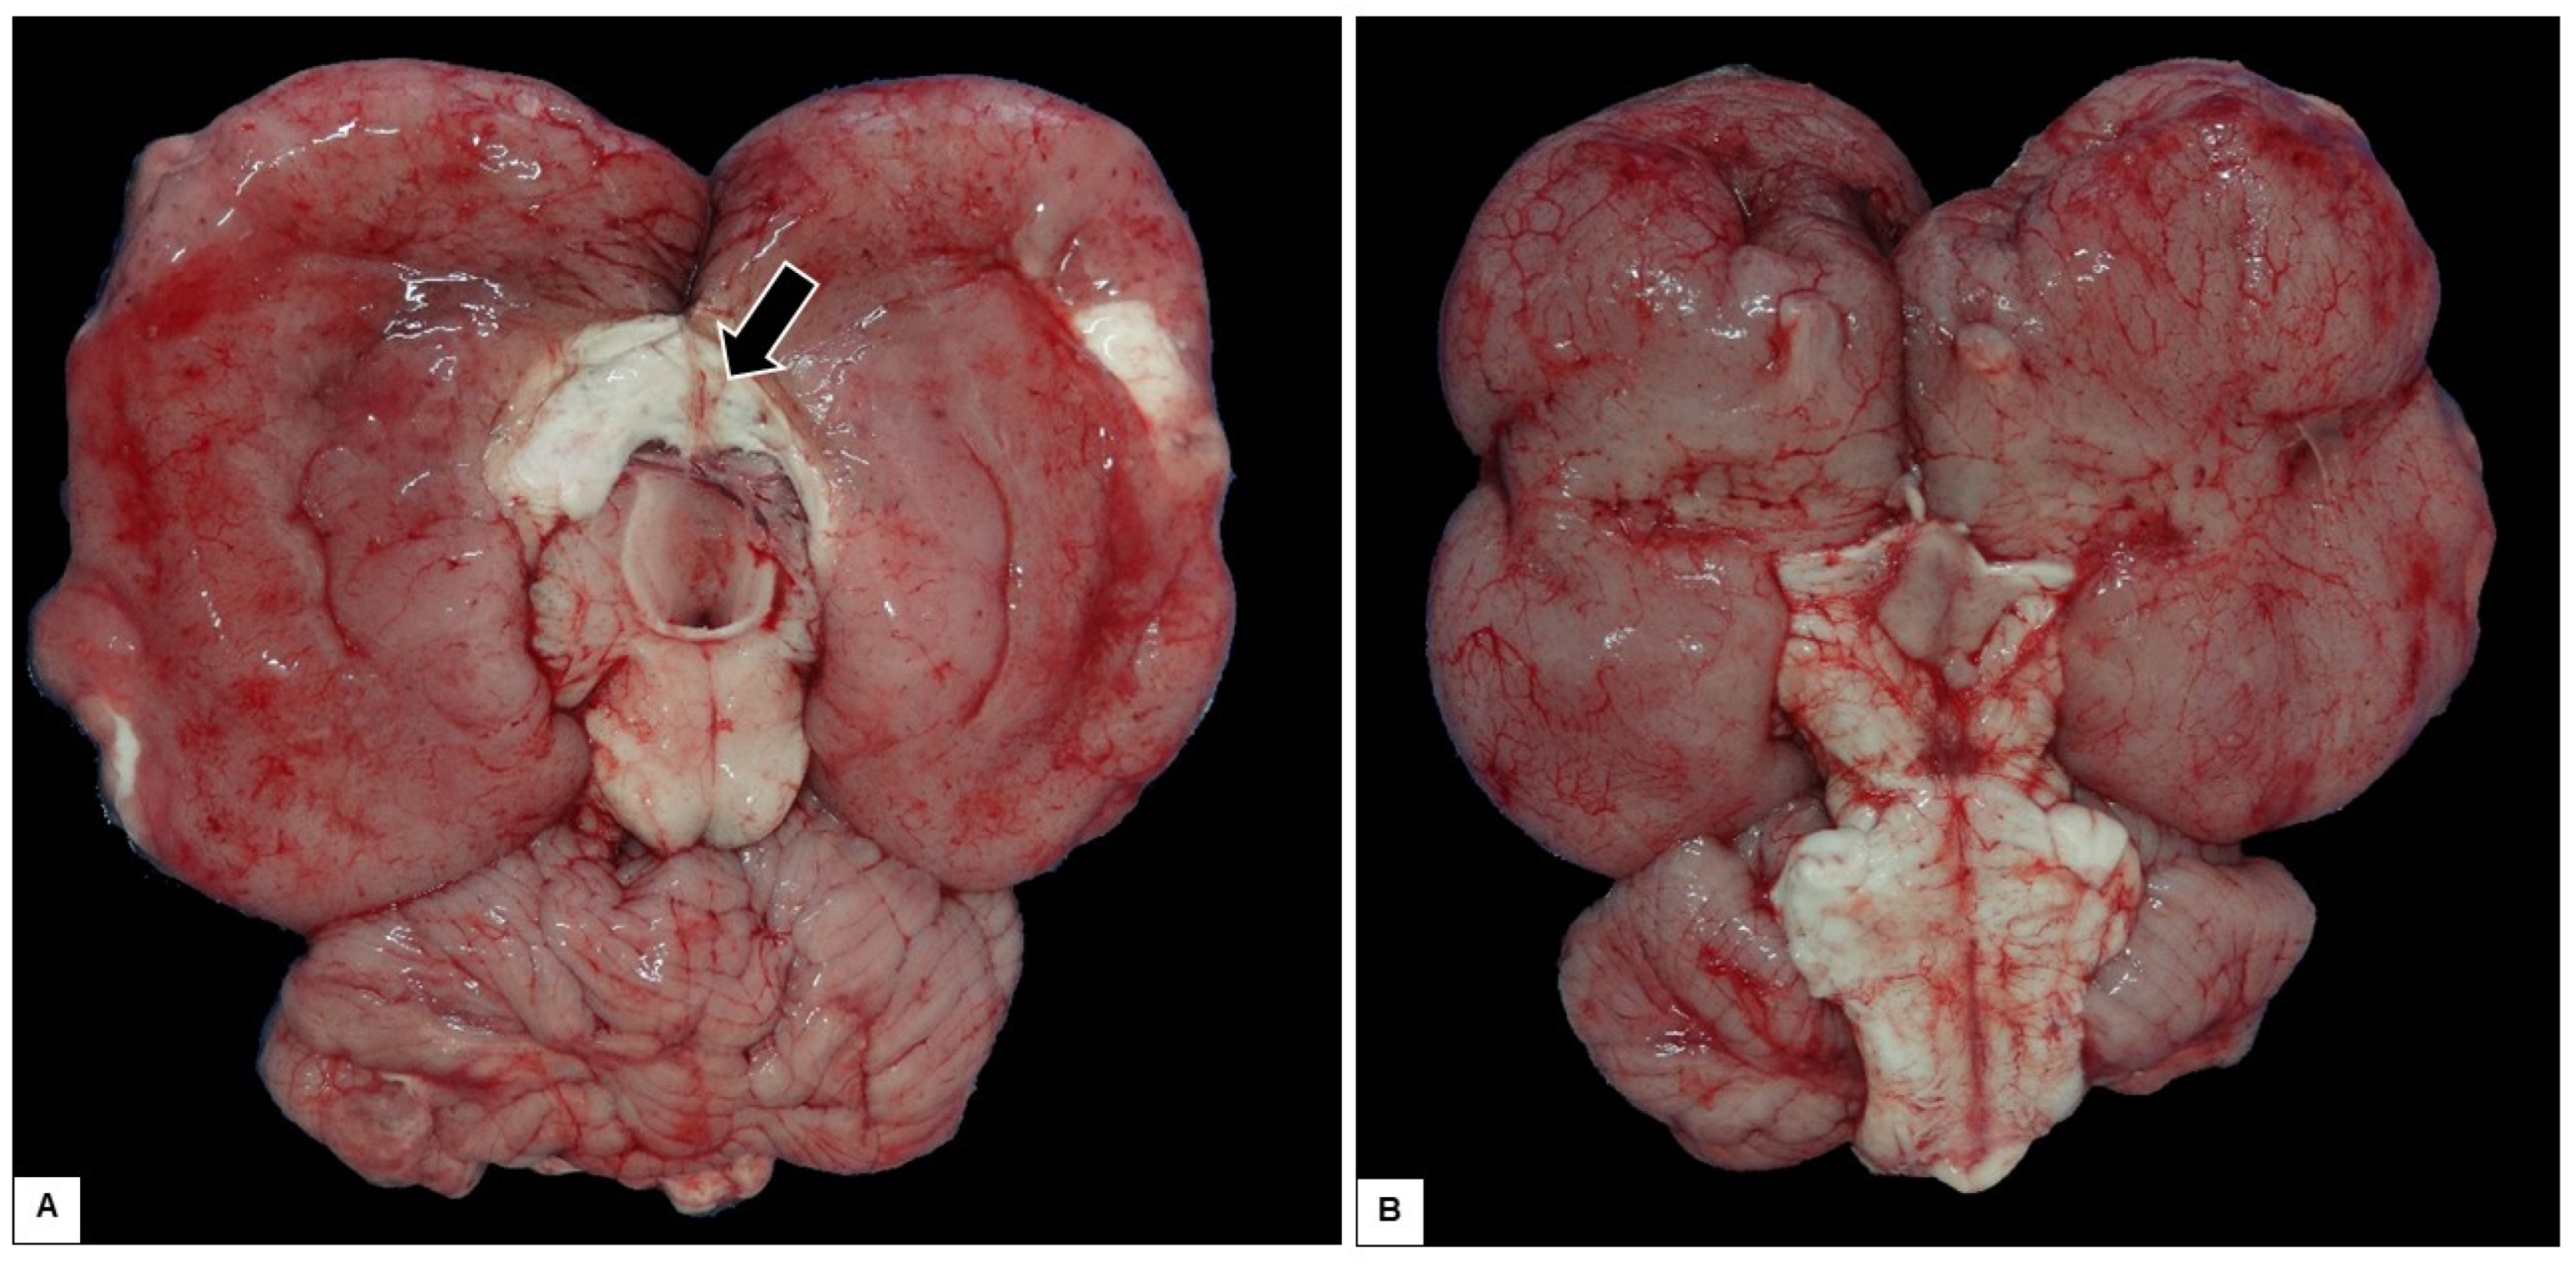

- Carvalho, V.L.; Groch, K.R.; Catão-Dias, J.L.; Meirelles, A.C.O.D.; Silva, C.P.N.; Monteiro, A.N.B.; Díaz-Delgado, J. Cerebral and cardiac congenital malformations in neonatal West Indian manatees (Trichechus manatus). J. Comp. Pathol. 2019, 166, 29–34. [Google Scholar] [CrossRef]